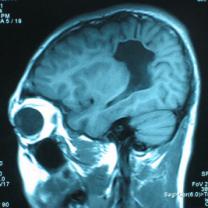

头颅CT和MRI可见颅骨缺损区下方软脑膜囊肿、脑软化灶或脑室穿通畸形(图2)。

图2:①和②CT及骨窗相显示右顶部颅骨缺损,其下方脑组织呈低密度改变;③-⑥MRI右顶局部颅骨缺如,脑组织轻度向外膨隆,右顶叶侧脑室体部旁局部脑组织缺如,代之以囊性长T1、长T2信号。